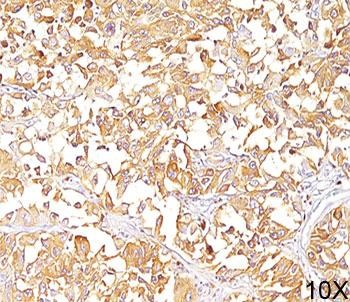

Product information "Anti-gp100, clone HMB45"

1 mg/ml in sterile PBS, BSA free, sodium azide free. Melanocytes produce organelles called melanosomes which produce melanin, the pigment that gives color to skin, hair, eyes, scales and feathers. gp100 was identified in an attempt to clone the gene Tyrosinase, an enzyme required for melanin synthesis. Further testing determined that gp100 is a melanoma-specific protein and is responsible for melanosome maturation, facilitating the transition from amorphous rounded vesicles to fibrillary ellipsoid organelles.Metastatic amelanotic melanoma can often be confused with a variety of poorly differentiated carcinomas, large cell lymphomas, and sarcomas using H & E stains alone. It is also difficult to differentiate melanoma from spindle cell carcinomas and various types of mesenchymal neoplasms. Clone HMB45 gp100 antibody stains fetal and neonatal melanocytes, junctional and blue nevus cells, and malignant melanoma. It also stains angiomyolipomas, tumors most commonly associated with the kidney. Intradermal nevi, normal adult melanocytes, and non-melanocytic cells are negative. This gp100 antibody does not stain tumor cells of epithelial, lymphoid, glial, or mesenchymal origin. Protein function: Plays a central role in the biogenesis of melanosomes. Involved in the maturation of melanosomes from stage I to II. The transition from stage I melanosomes to stage II melanosomes involves an elongation of the vesicle, and the appearance within of distinct fibrillar structures. Release of the soluble form, ME20-S, could protect tumor cells from antibody mediated immunity. [The UniProt Consortium]

| Application: | WB, FC, IHC, IF |